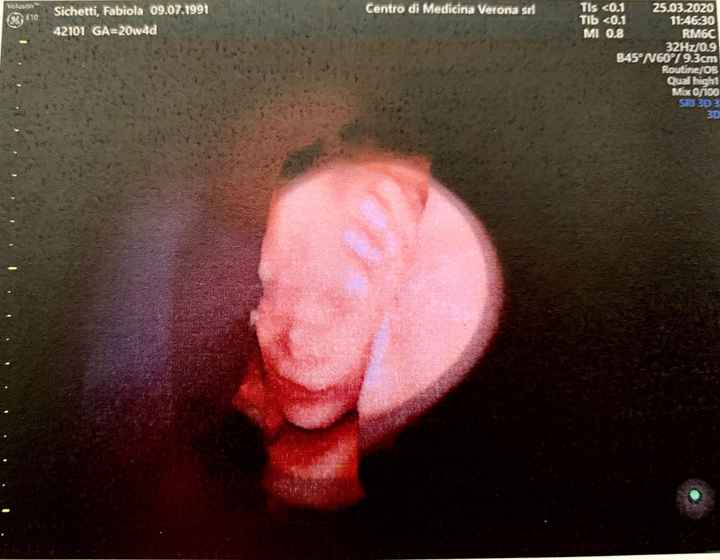

'Verona', Verona ยท Da Agosto 2018

15 Giugno 2019